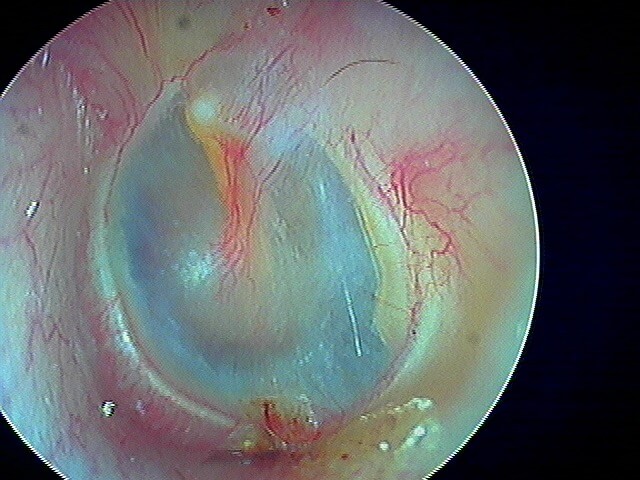

3/2 barotraumatique

– stade I : hyperhémie du manche du marteau et de la pars flaccida ;

– stade II : tympan rétracté, congestif, immobile

– stade III : aspect d'otite séromuqueuse

– stade IV : aspect otite séro-hémorragique, otohématome

– stade V : perforation

Ici des stades V perforés